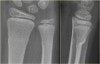

X-ray에서 buckle은 미세할 수 있으며 종종 오직 한가지 영상에서 보입니다.

X-ray : 융기 골절(Torus fracture, Buckle fracture)